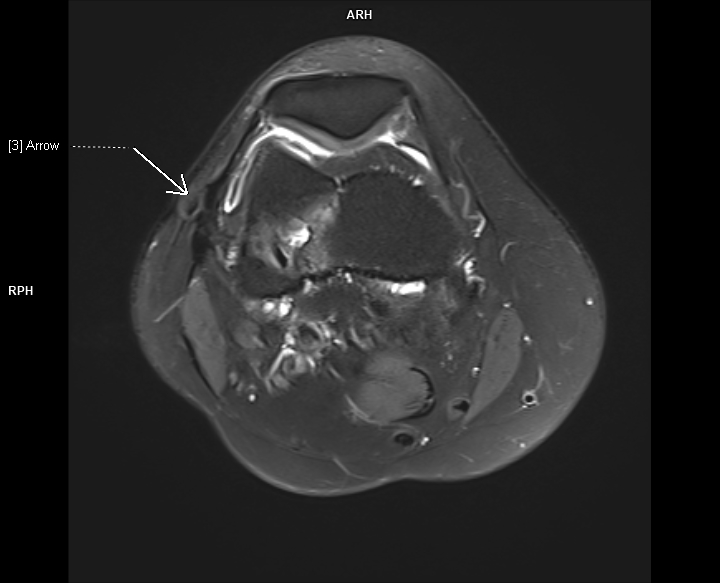

Figurile 1-3:  axial PD cu cu saturaţia grăsimii

Discuţie caz nr 107: la nivelul platoului tibial și posterior la nivelul condilului femural extern se evidențiază modificări de tip chistic în osul subcondral. În plus, a nivelul ligamentului colateral lateral se evidențiază o plajă limitată de lipsă de substanță în dreptul unei plaje de lipsă de substanță osoasă din condilul femural extern care este plombată postoperator.